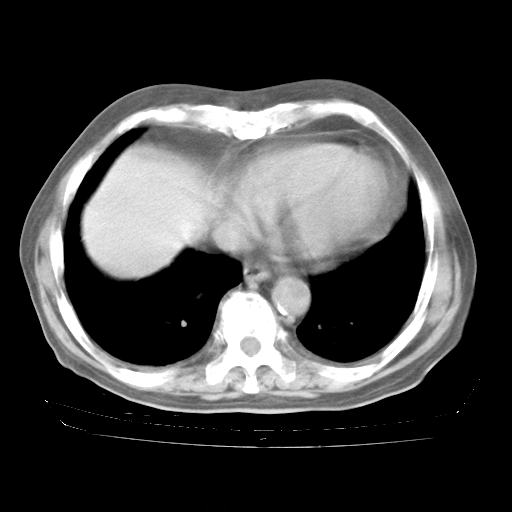

4月28日肺部CT——再次出现类似去年5月9日——透光度降低,“间质性”改变。

4月28日肺部CT——再次出现类似去年5月9日——磨玻璃样、间有“粟粒样”改变。